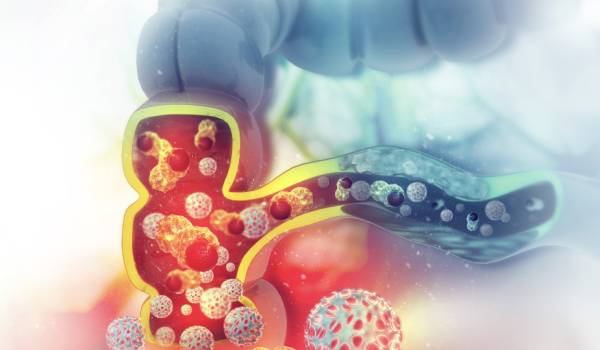

El cáncer colorrectal no cause síntomas enseguida.

Tratamiento de apendicitis aguda, la diverticulitis, el prolapso rectal, el cáncer de colon